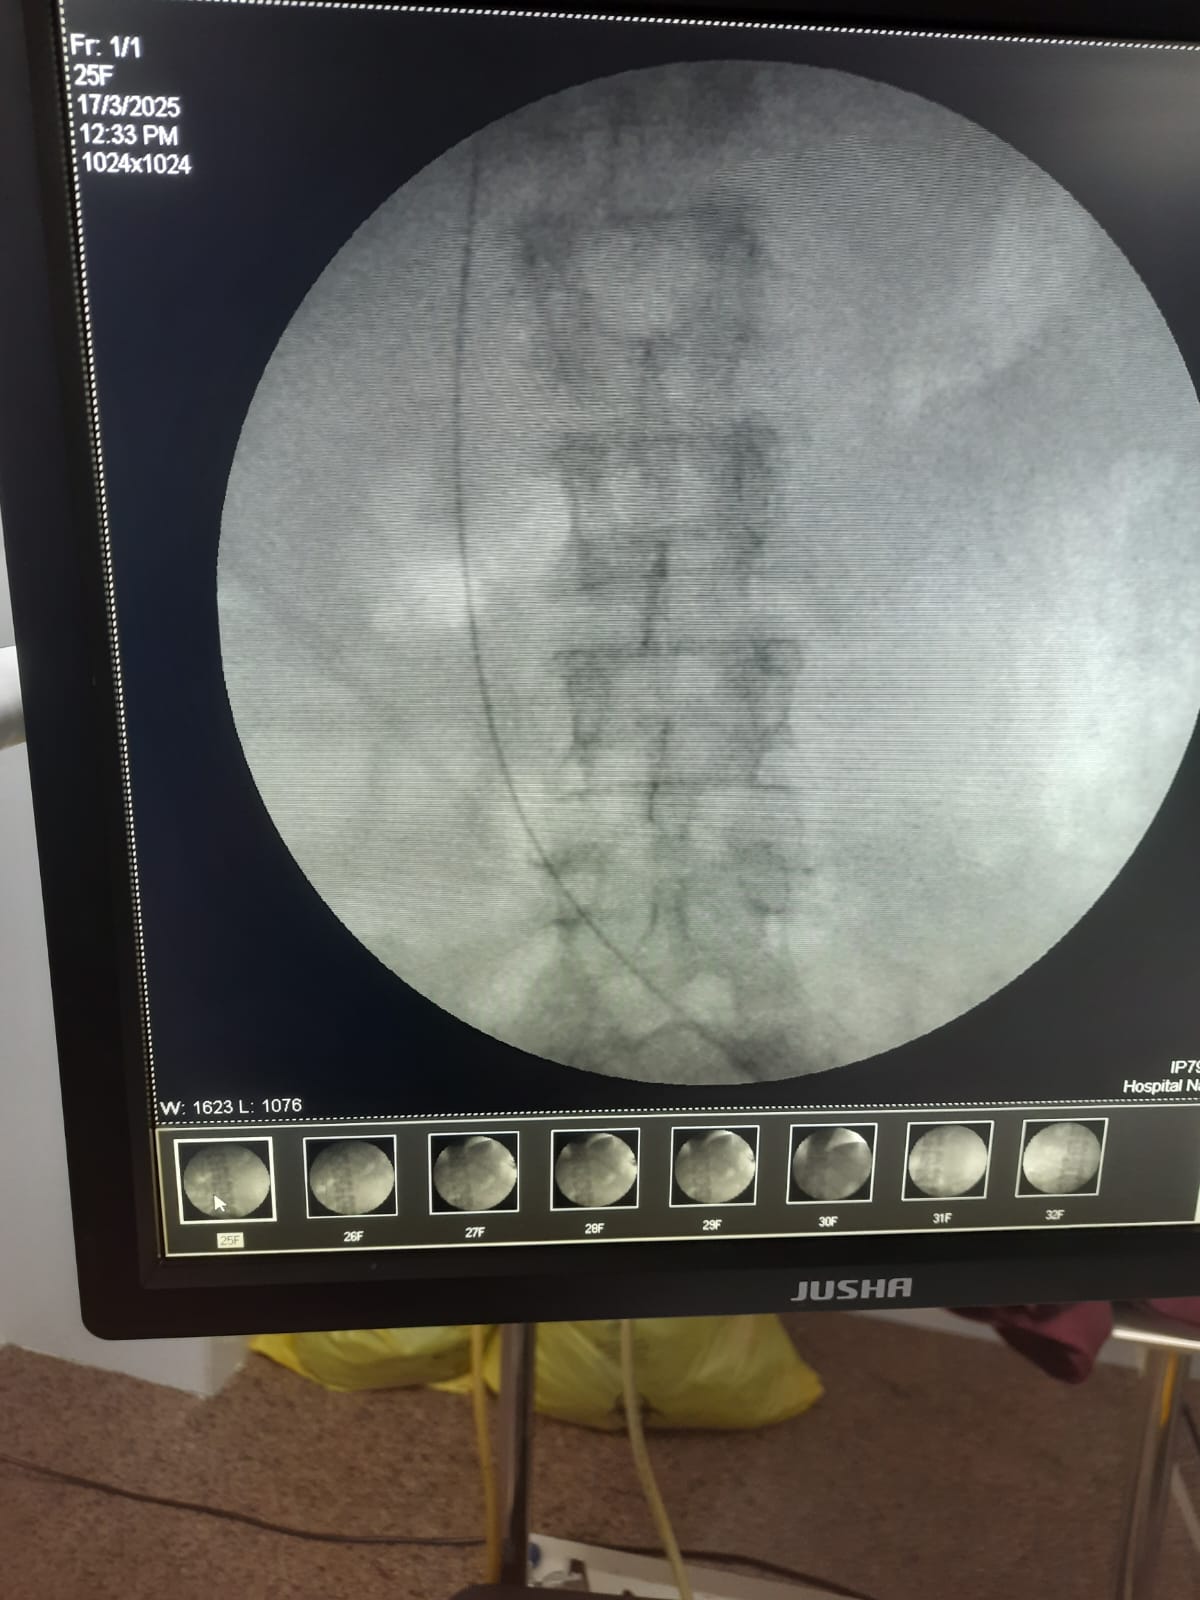

Following the easy passage of the hydrophilic wire, a 3Fr ureteric stent was passed over it. The stent advanced without resistance, but the proximal pigtail did not coil in the renal pelvis, heightening the suspicion of misplacement. An immediate post-procedure CT scan confirmed the stent's location: the distal end was correctly within the bladder, but the main body and proximal end were located outside the ureter, passing into the Inferior Vena Cava. However, further investigation with MRI of Abdomen revealed that the stent had migrated from the bladder to the left internal iliac vein and reached in the Right Atrium. The patient remained hemodynamically stable. A team meeting was sought, including the opinions of the Cardiologist, Cardiothoracic surgeon, and Urologist, and came to a conclusion that a attempt via endovascular retrieval of the stent. Initial attempts by interventional cardiology via the femoral vein to the Right Atrium failed. Successful retrieval was achieved by an alternative access via the right internal jugular vein, direct entry into the left internal iliac vein. A snare catheter was skillfully deployed to secure the distal end of the DJ stent. The stent was removed successfully without any immediate vascular complication. The patient was monitored in the MICU post-procedure. On the second day post procedure, patient developed mild hematuria and was treated conservatively, and repeat CT KUB with contrast was done, which did not show any remnant fistula.